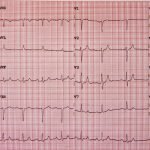

Hyperkalemia on ECG

Initial ECG shows tall, peaked T waves, most prominently in V3 and V4, as well as QRS widening. These findings are consistent with hyperkalemia, which was promptly treated. Follow-up ECG post-treatment shows narrowing of the QRS complexes and normalization of peaked T waves.

The etiology of hyperkalemia may be due to an acute insult such as crush injury, drug side effect, or in acute renal failure, but may also occur in the setting of a chronic insult such as chronic kidney disease.1 As potassium rises, several abnormalities can be identified on ECG. Initially the T waves become peaked and the QRS complexes widen.2,3 This can devolve into a wide complex rhythm, ventricular tachycardia, ventricular fibrillation, or asystole. Patients may also experience systemic symptoms such as weakness or paralysis.1 In this particular case, labs showed a potassium of 7.6-mmol/L after initial treatment (see repeat EKG). While the incidence of hyperkalemia in the general population is not defined, the incidence in hospitalized patients is 1.3-10%.4-8 Impaired kidney function is the most common risk factor found in 33-83% of affected patients.4,5,8,9 Treatment for hyperkalemia generally includes IV insulin and IV dextrose and nebulized albuterol for intracellular shift of potassium, IV furosemide and IV fluids for dilution and renal excretion of furosemide, and IV calcium for stabilization of cardiac membranes.2,3